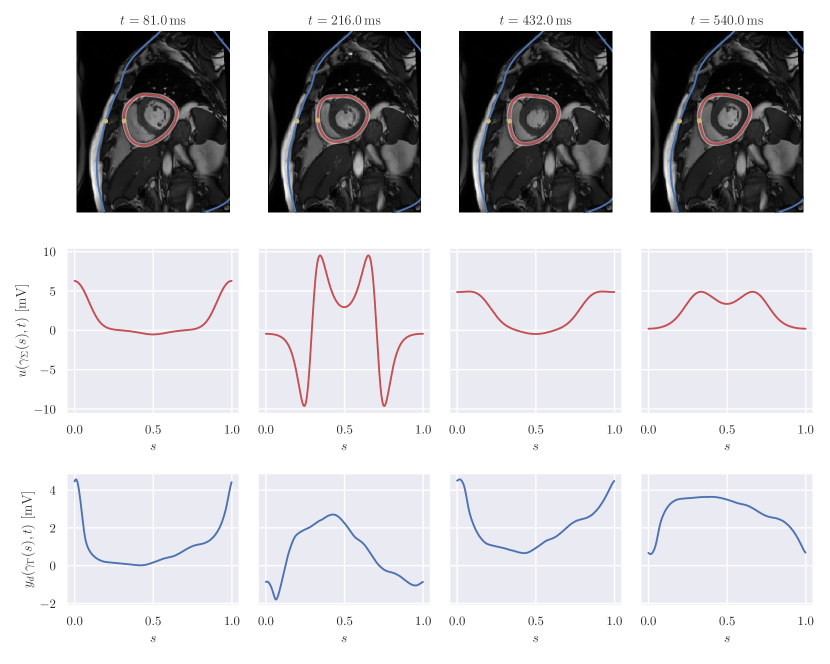

In this section we present numerical experiments to assess the validity of the approach. To obtain a space-time reference torso anatomy, we have segmented cardiac magnetic resonance (CMR) imaging data previously acquired [40]. The temporal image stack was obtained from a cine ECG-triggered segmented steady-state free precession sequence in mid-ventricular short-axis orientation. Slice thickness and voxel resolution were and , respectively. The 25-phase temporal stack covered the whole heart beat, with an RR interval on the surface ECG of ). Images were reordered such that the first image at corresponded to the diastole, defined by the maximal left ventricular cavity volume. The systole, defined by the minimum cavity volume, occurred at . The segmentation was performed by manual contour tracing of the epicardium for each image. In order to end up with a smooth computational domain, we performed a least-squares fit of the contours using a truncated Fourier series with a threshold of in the relative root-mean-square error. Finally, we interpolated the extracted shapes to get a pericardial representation at 50 time instants. The chest was also previously segmented from ultra-fast gradient-echo “VIBE” images in axial, coronal, and sagittal orientations to produce a smooth 3-dimensional closed surface modelled in Blender222https://www.blender.org. As shown in Figure 1, the contour of the chest was eventually obtained by intersecting the chest surface with the orientation plane of the pericardium.

In Figure 2, we summarised the input data for the forward and inverse problem and the geometry of the pericardium, superimposed with the CMR images. To model the uncertainty, we selected the resulting reference shape of the pericardium , for , as the space-time mean of the random deformation field . The covariance of evaluated at the points with and with was the product of a matrix-valued kernel in space and a scalar kernel in time. For the spatial component of the covariance, we considered the Matérn kernel

In the forward problem, the pericardial potential was defined analytically as a -periodic function in the variable . For convenience, we set , being the normalised curvilinear coordinate. We simulated a left bundle branch block, that is the extracellular potential consisted in a propagation from free wall of the right ventricle, at , towards the free wall of the left ventricle, at . The propagation took , consistent with a long QRS complex. The specific analytical form of is given in Appendix B.

To generate the input data for the inverse problem, we computed the solution of the forward problem on the space-time reference geometry and eventually added Gaussian noise with zero mean and variance , corresponding to a signal-to-noise ratio of approximately .